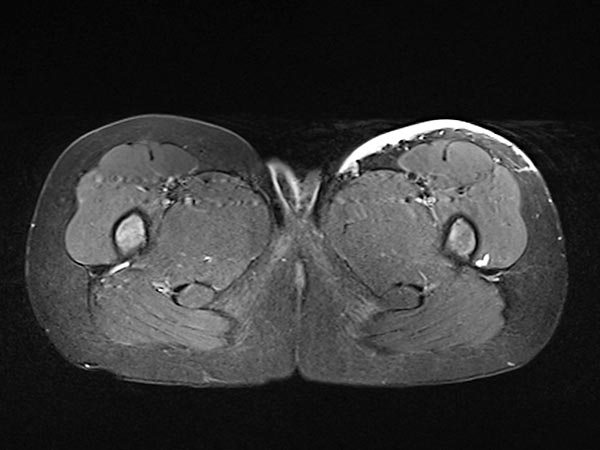

Auch in der axialen Schichtführung der MRT (T2-gewichtet, fettgesättigt) ist die Infiltration der Muskulatur durch die Raumforderung gut dargestellt. Auch Hämangiome können als vaskuläre Tumoren eine solche Infiltration aufweisen, ohne dass sie maligne sein müssen.

In der nativen koronaren T1-gewichteten MRT ist der Tumor isointens zur Muskulatur ohne enthaltene Fettgewebsanteile. Er ist somit in dieser Sequenz kaum von der Muskulatur abgrenzbar.

Die axiale T2-Wichtung ohne Fettsättigung zeigt den Tumor homogen nur gering hyperintens. Er ist zwar hyperintenser als Muskulatur, aber insgesamt deutlich weniger hyperintens als das umgebende subkutane Fettgewebe.